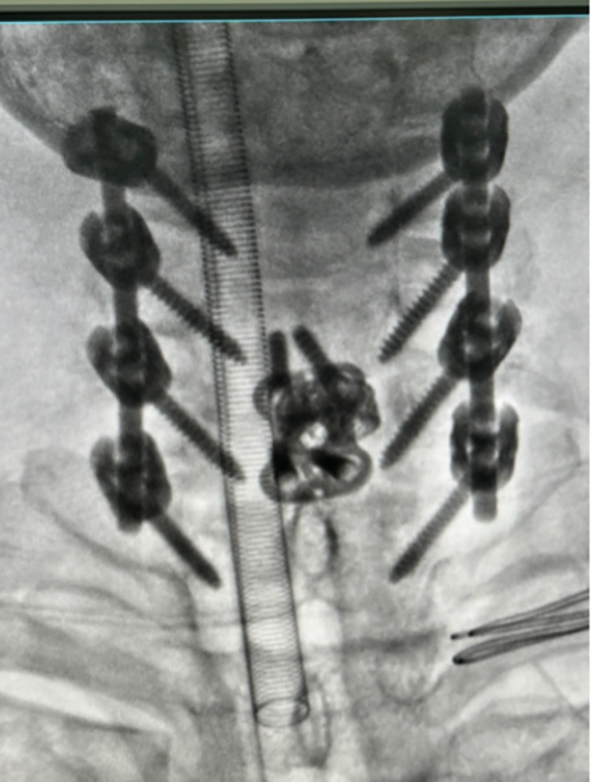

8月29日,创伤中心专家团队为患者实施了一期手术。主任医师张鹏、副主任医师陶扶林与全体医护人员齐心协力,小心翼翼地搬动患者并帮助其翻身。手术采用俯卧位,通过颈椎后路,解除C6/C7关节突绞索状态,恢复正常的颈椎序列。同时,手术全程进行神经电生理监测,确保手术操作不会造成颈髓损伤。术中固定C5-T1脊柱节段,咬除C5-C7椎板,彻底减压,解除颈髓压迫。手术持续3小时,全程在电生理监测下顺利完成,患者颈髓未发生二次损伤,苏醒后肢体活动同术前。